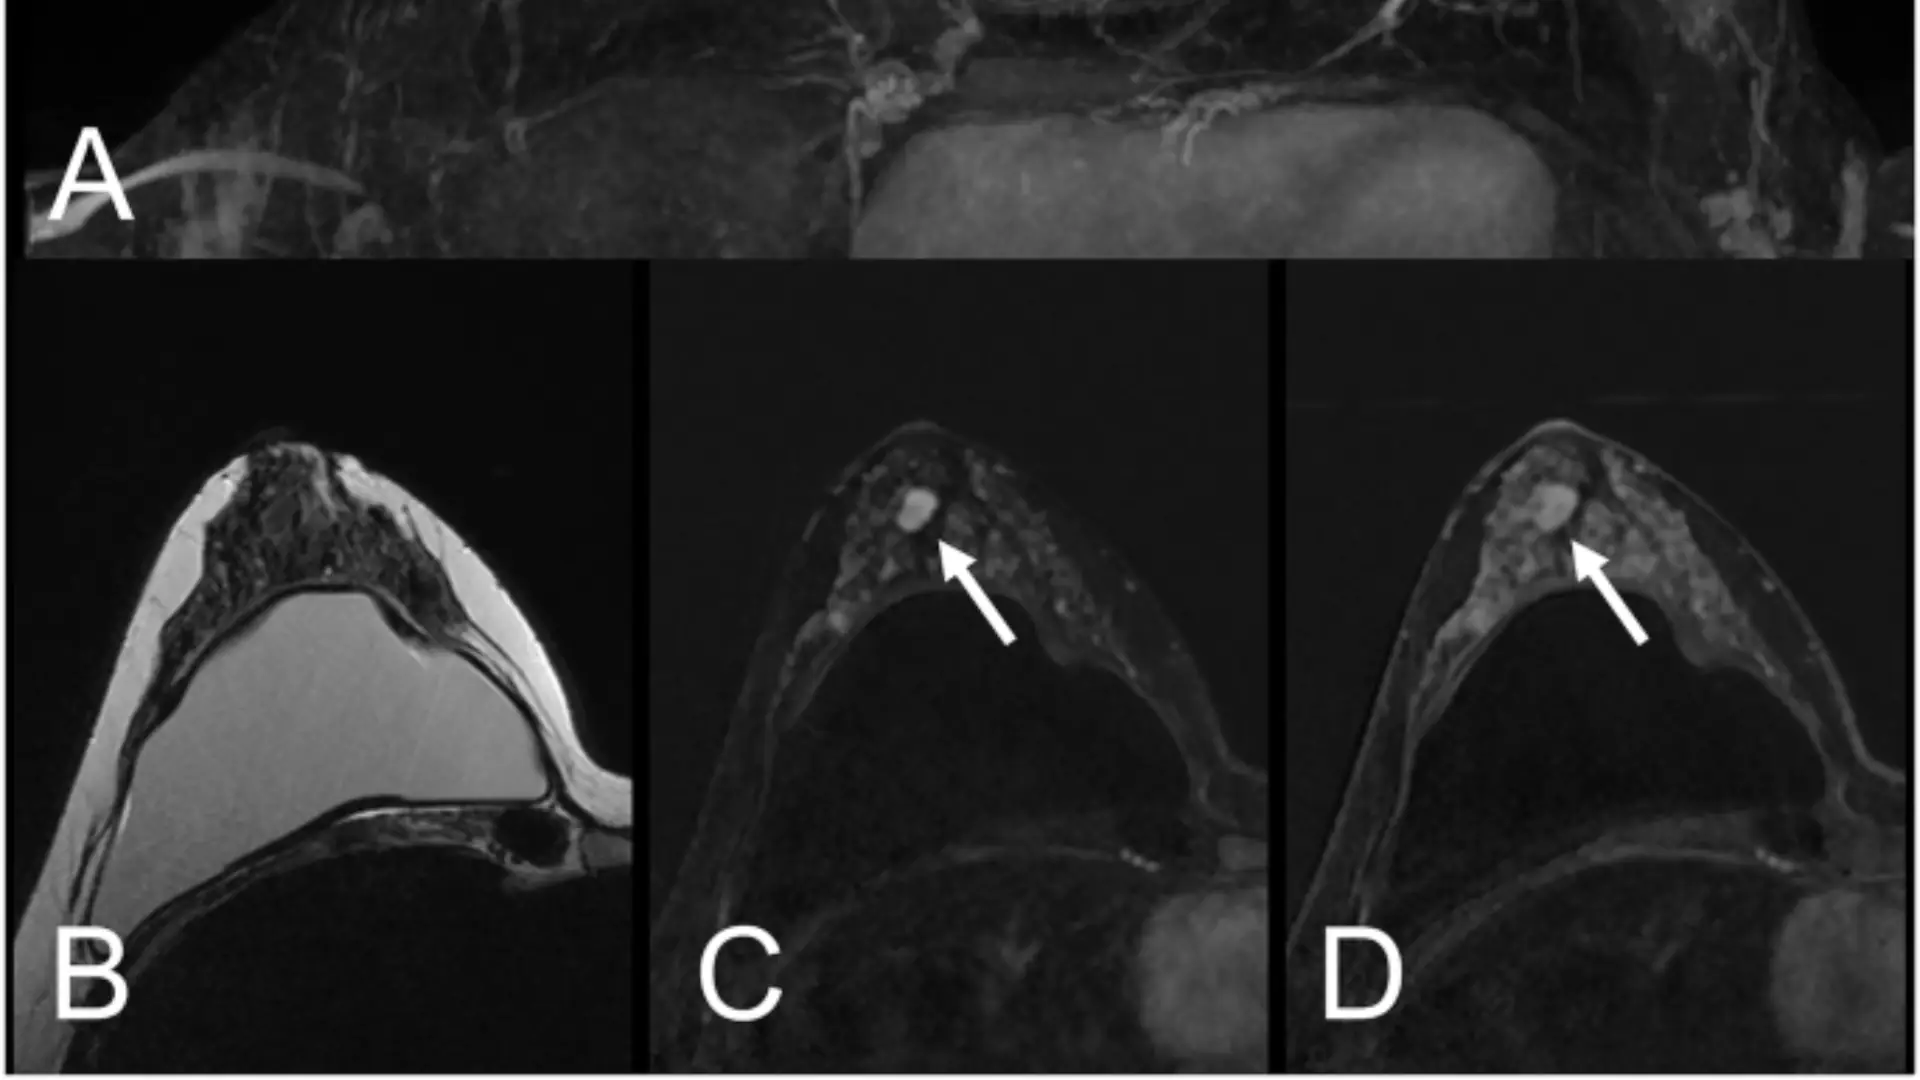

El estudio prospectivo aleatorizado incluyó 55 pacientes, con una mediana de edad de 70 años, portadores de 58 lesiones clasificadas como PI-RADS 3 o superiores. Los investigadores compararon dos modalidades de ablación focal con láser: una utilizando una sola fibra y otra con multifibra.

Se utilizó MRI para planificar el procedimiento y fusionar imágenes, permitiendo ajustar la posición de la aguja y asegurar la cobertura del volumen tumoral. La micro-ecografía, gracias a su alta resolución, facilitó la localización precisa de los focos cancerígenos, alcanzando una tasa de detección del 91 por ciento.

Durante el estudio, se monitorearon los niveles de PSA y se evaluó la recurrencia tumoral a los 12 meses de seguimiento. Los pacientes presentaban, en su mayoría, lesiones con Gleason 3+4, mientras que un porcentaje menor tenía Gleason 3+3.